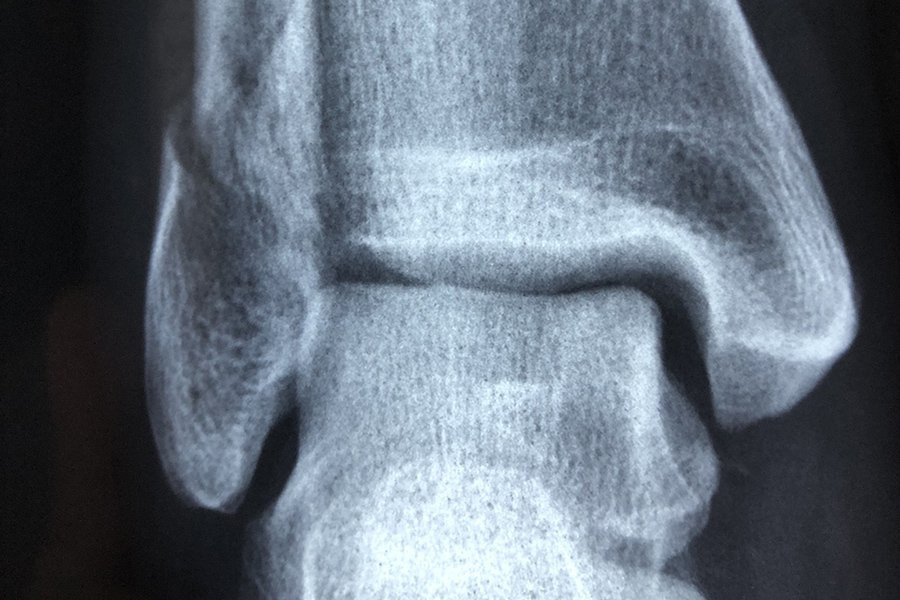

Команда, в которую вошли исследователи из ANU и больницы Канберры, собрала КТ-снимки у большой выборки здоровых людей и пациентов, ожидающих замены коленного сустава.

Используя передовые методы анализа изображений для создания 3D-моделей сотен костей коленной чашечки, команда затем применила методы моделирования формы для визуализации и измерения формы поверхностей коленной чашечки в трех измерениях.

Хотя они не нашли уникальных особенностей среди коленных чашечек женщин по сравнению с мужчинами, они обнаружили изменения в поверхностях коленной чашечки, которые были более выражены у людей с остеоартритом.

«Удивительно то, что различные суставные поверхности коленной чашечки по-разному меняют форму при остеоартрите и по мере увеличения тяжести заболевания», — сказала Уилсон.